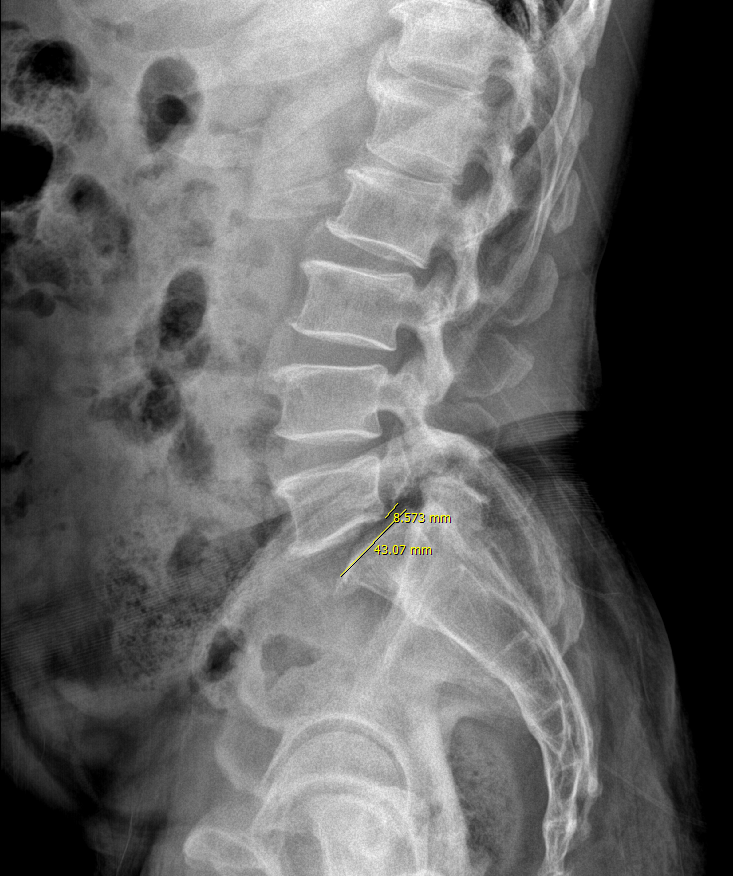

이 분은 21년에 요통으로 내원하신 분입니다. (개인정보가 특정되지 않으니 공유해도 상관없는 것으로 아는데, 문제가 되면 삭제하겠습니다.)

대략적으로 재어보니 grade 1에 해당하고, 파행을 포함하여 심각한 수준의 신경학적 증상은 없었습니다.

꾸준히 보존적 치료 받으면서 증상을 보자고 했습니다.